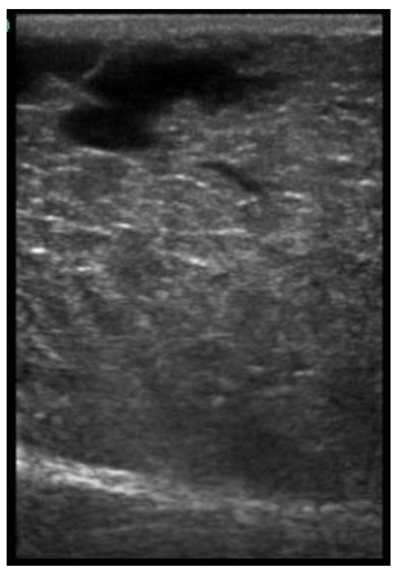

| 113 days of pregnancy (P113) Scanning depth 4.7 cm | ![]() | ![]() | MT generous: 28.9 mm MT conservative: 25.9 mm Gland cistern: 3.3 mm Parenchyma: 10.9 mm Fat Pad: 10.0 mm |